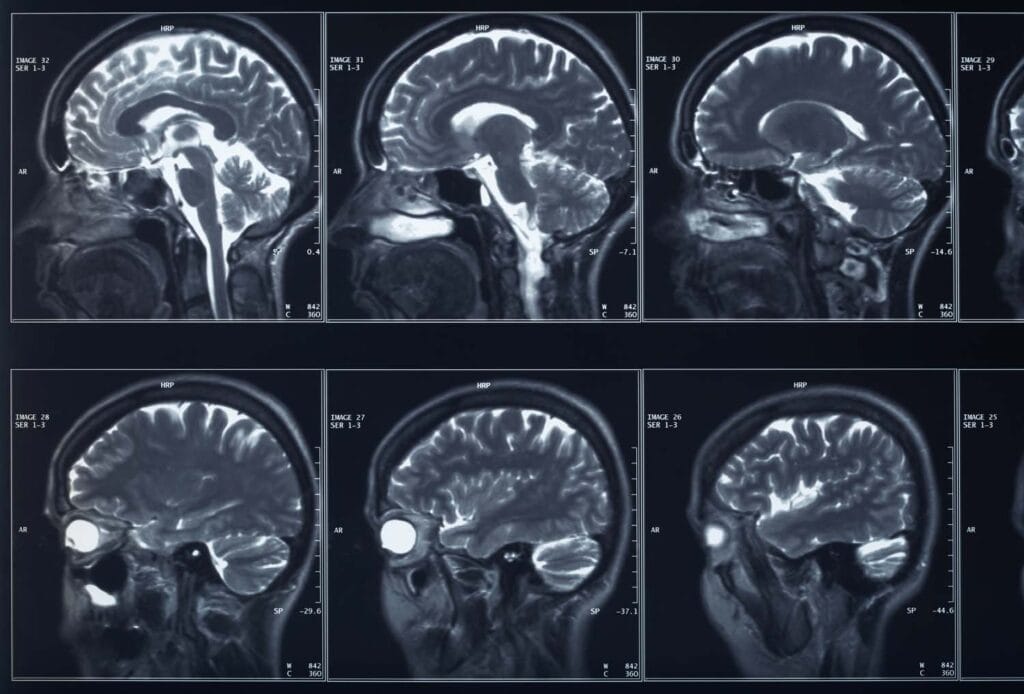

Concussions and subconcussive impacts sustained in American football have been associated with short- and long-term neurological impairment, but differences in head impact outcomes across playing positions are not well understood.

The American Medical Society for Sports Medicine has identified playing position as a key risk factor for concussion in football and one for which additional research is needed. This study examined variation in head impact outcomes across primary football playing positions in a group of 730 National Collegiate Athletic Association Division I Football Championship Series athletes, using a self-report questionnaire.

Although there were no significant differences between position groups in the number of diagnosed concussions during the 2012 football season, there were significant differences between groups in undiagnosed concussions (p=0.008) and “dings” (p<0.001); offensive linemen reported significantly higher numbers than most other positions.

Significant differences were found between position groups in the frequencies of several postimpact symptoms, including dizziness (p<0.001), headache (p<0.001), and seeing stars (p<0.001) during the 2012 football season, with offensive linemen reporting significantly more symptoms compared to most other groups. There were also positional differences in frequency of returning to play while symptomatic (p<0.001) and frequency of participating in full-contact practice (p<0.001). Offensive linemen reported having returned to play while experiencing symptoms more frequently and participating in more full-contact practices than other groups.

These findings suggest that offensive linemen, a position group that experiences frequent, but low-magnitude, head impacts, develop more postimpact symptoms than other playing positions, but do not report these symptoms as a concussion.